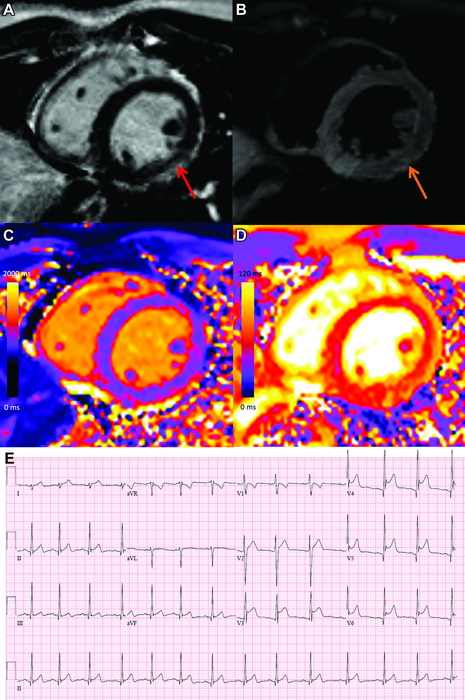

COVID-19 vaccine associated myocarditis. Short-axis 1.5T MRI images and ECG findings of a 19-year-old man with myopericarditis who presented with chest pain 3 days following the second dose of an mRNA COVID-19 vaccine (mRNA-1273). Cardiac MRI performed 2 days after symptom onset demonstrates mid wall to subepicardial late gadolinium enhancement (LGE) at the basal to mid inferior lateral wall with adjacent pericardial enhancement (A, red arrow), corresponding hyperintensity on T2-weighted imaging (B, orange arrows), abnormal high native T1 (C, 1095 ms, maximum region of interest), and abnormal high native T2 (D, 57 ms, maximum region of interest). The ECG demonstrates diffuse concave upward ST segment elevation except in leads aVR and V1, upright T waves in the leads with ST segment elevation, and PR depression, consistent with pericarditis (E). Peak high sensitivity troponin-I was 5772 pg/mL. He was admitted to hospital and was discharged after two days following complete resolution of his symptoms. At short-interval follow-up he was asymptomatic with normal troponin levels. Image courtesy of the Radiological Society of North America

1. MRI Sheds Light on COVID Vaccine-Associated Heart Muscle Injury